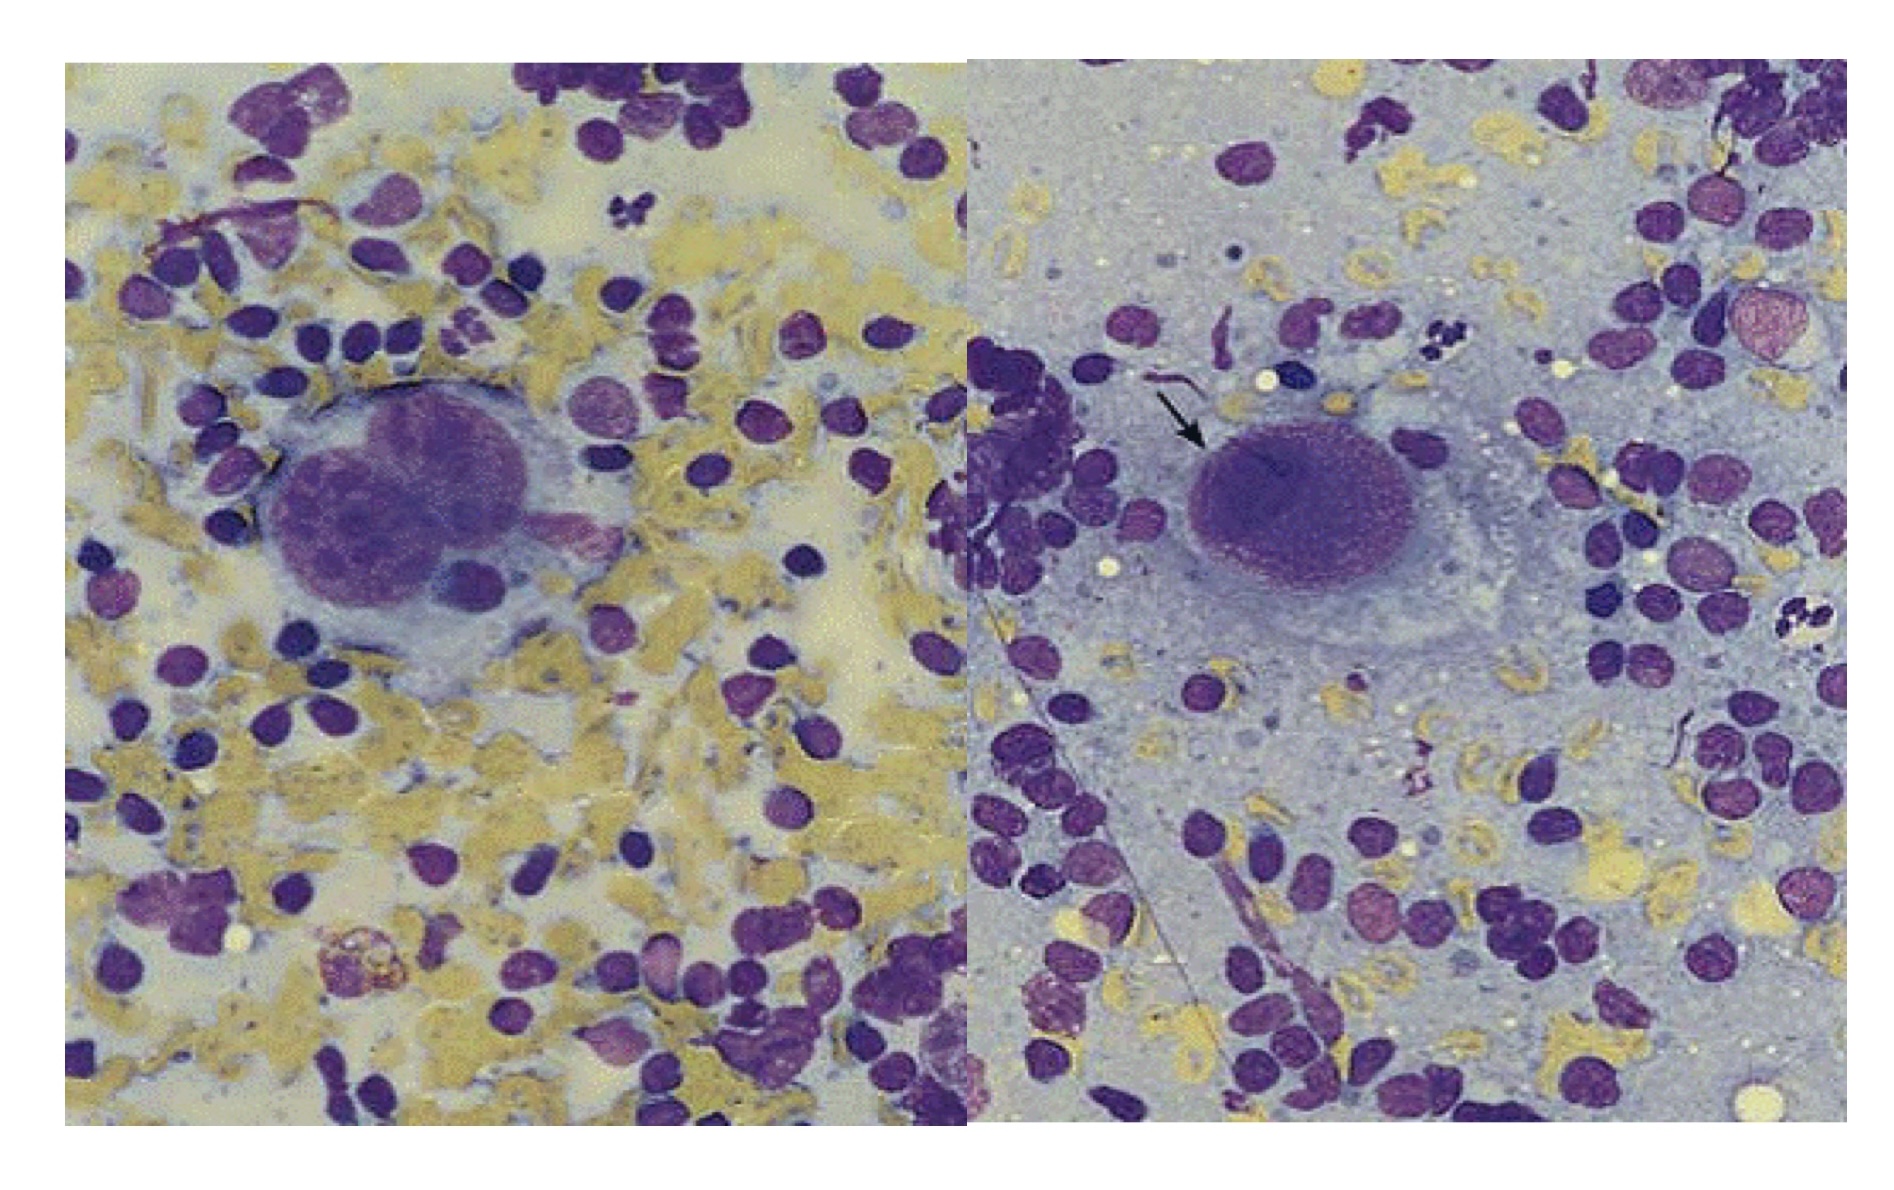

Hồng cầu lưới (Reticulocyte)

Là hồng cầu được phóng thích từ tủy xương vào tuần hoàn máu một ngày trước khi nó mất RNA còn lại để trờ thành HC trưởng thành.

Tuỷ xương bình thường có khả năng đáp ứng thiếu máu bởi tăng HCL từ 6-8 lần.

- Nếu thiếu máu do giảm sản xuất từ tủy xương thì HCL giảm.

- Nếu thiếu máu do tăng phá hủy HC hoặc mất máu thì HC lưới tăng cao

Tủy bình thường hoặc suy tủy không thấy HCL được

HC lưới tăng khi mất máu đột ngột phải huy động HC ở tủy vào máu hoặc khi có bệnh lý ác tính khi các dòng HC tăng sinh quá mức

Đếm số lượng HC lưới

Bình thường, SLHC lưới khoảng 0.5-1.5%

Số lượng tuyệt đối:

- 0.5% X 5,000,000/mm3 = 25,000/mm3

- 1.5% X 5,000,000/mm3 = 75,000/mm3

- 25.000 → 75.000/mm3

Hiệu chỉnh số lượng HC lưới (RI)

- Theo Hb: Hb b/n x HC lưới / 12g/dl

- Theo Hct: Hct b/n x HC lưới/ 45%

- Kết quả:

2 → tủy có đáp ứng với thiếu máu

- ≤ 2 → tủy kém đáp ứng với thiếu máu có đáp ứng với tình trạng thiếu máu hay ko?